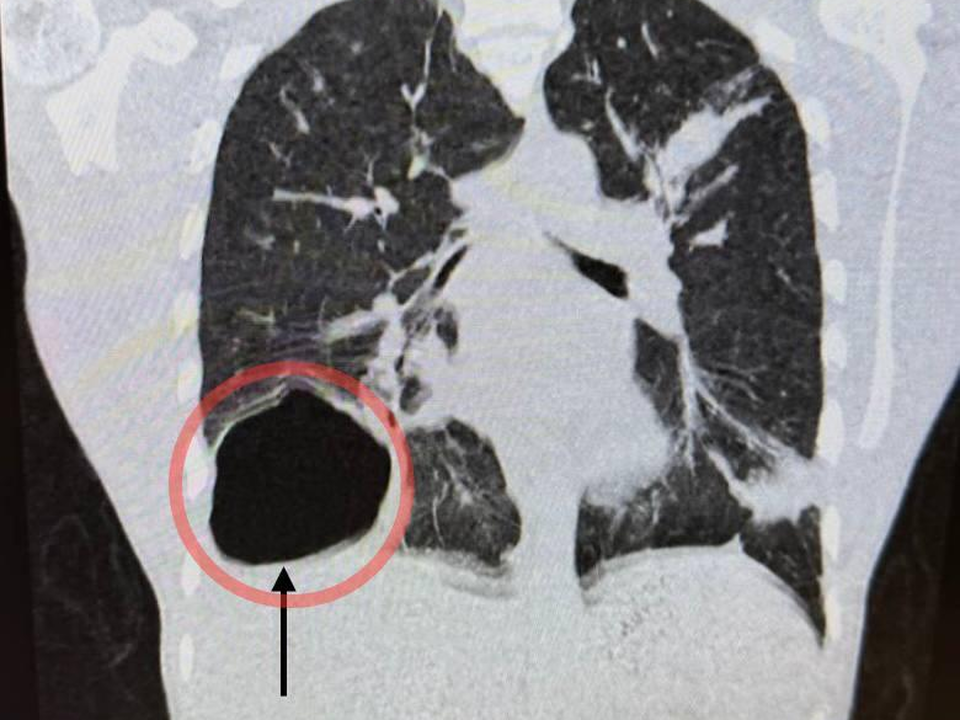

В Московский областной центр охраны материнства и детства (МОЦОМД) поступил 17-летний юноша с жалобами на слабость, высокую температуру, кашель и боль в правой половине грудной клетки. Проведенная диагностика выявила крупную паразитарную кисту правого легкого. Ее размер был сопоставим с размером головы новорожденного ребенка. Киста образовалась из-за попадания в организм гельминта — эхинококка.

«После подтверждения диагноза с помощью лабораторного контроля и компьютерной томографии мы приняли решение о проведении операции. В нашем отделении накоплен большой опыт хирургического лечения данной патологии малоинвазивными методами через несколько проколов. Такая щадящая операция сильно сокращает травматичность вмешательства и сроки реабилитации. В данном случае мы избежали широкого разреза. Операция прошла успешно, послеоперационный период протекал без особенностей», — рассказал заведующий отделением детской хирургии Владимир Трунов.